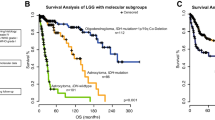

Oncoplot of available tissue data with overall survival (OS) after surgery in different patient groups in the patient cohort. A: Consecutive patients are listed horizontally in chronological order (time of surgery from 2017 to 2022). NGS = Next-generation sequencing. mTOR-P-IHC = Phospho-mTOR Immunohistochemistry. IDH = isocitrate dehydrogenase. CDK4/6i = Cycline-dependent Kinase 4/6 inhibitors. mTORi = mammalian target of rapamycin inhibitor. PARPi = Poly (ADP-ribose) polymerase inhibitor. MEKi = Mitogen-activated protein kinase kinase inhibitor. GTR = Gross Total Resection, STR = Subtotal resection B: All patients in the cohort (median survival 399 days). C: Survival after surgery based on WHO classification grades (WHO 2: undefined, WHO 3: undefined, WHO 4, isocitrate dehydrogenase wild type, IDH-WT: 334 days, WHO 4, IDH-mut: 197 days. D: Survival in GBM, IDH-WT patients after gross total resection (GTR, 348 days) vs all other surgical modalities (subtotal resection – STR and biopsies, survival undefined) in this cohort, p = 0.04, Gehan-Breslow-Wilcoxon test

Next, we examined the post-surgery survival of the patients of this cohort. At the time of this analysis, 44 of 70 patients were censored. Across all tumor types and WHO grades, the median survival after repeat surgery was 399 days (Fig. 3B), indicating a median survival long enough for patients to benefit from the personalized targeted therapies that were determined based on the sampled tumor tissue. As expected, patients with WHO grade 4 tumors showed the worst survival after surgery, compared to WHO grade 2 and grade 3 tumors (348 days in WHO grade 4 vs. undefined in other groups, p = 0.03, Gehan-Breslow-Wilcoxon test, Fig. 3C). Indeed, patients with IDH-wildtype GBM conferred a post-surgery survival rate of 334 days. To confirm the prognostic benefit of GTR in the context of this study, we compared survival after repeat surgery in GBM patients undergoing GTR (348 days, n = 34) to that of all other GBM patients (undergoing STR, open or stereotactic biopsies), with undefined survival due to small sample size in the latter (n = 10, p = 0.04, Gehan-Breslow-Wilcoxon test, Fig. 3D).